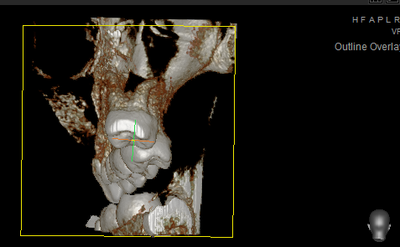

Ну, компьютерную томографию (3D объемный снимок) можно сделать - где угодно.

А для того, что ортопантомография (ОПТГ, обзорный или панорамный снимок зубов), является плоскостным, а значит происходит наложение каждой детали снимка послойно друг на друга. Следовательно, рассмотреть объект исследования, в частности, область зуба мудрости, расположенного рядом нижнечелюстного нерва, во всех плоскостях, под иным углом или другой проекции невозможно. КЛКТ (Конусно-лучевая компьютерная томография), напротив дает нам такую возможность.